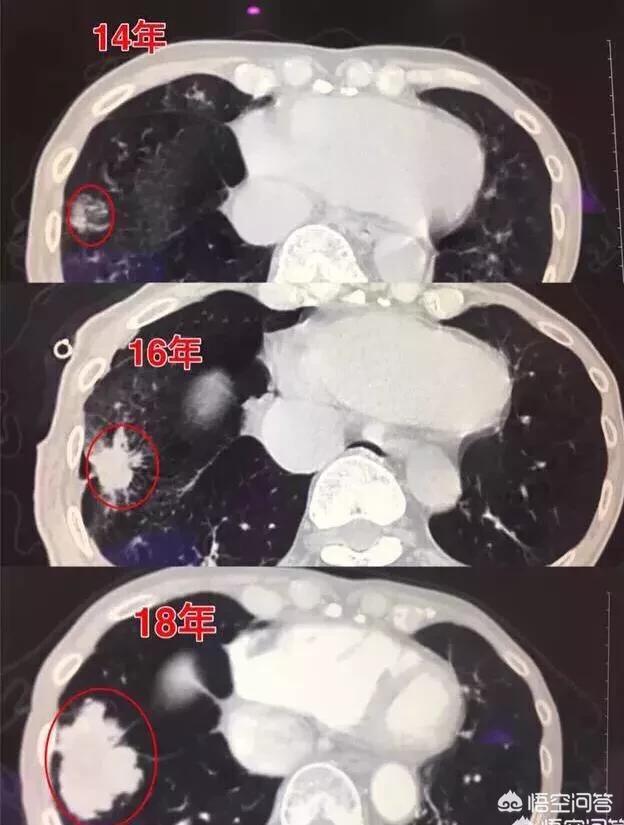

Antécédents de croissance d'un petit nodule pulmonaire qui s'est transformé en cancer du poumon

Il y a deux jours, j'ai lu un cas, le patient, un homme de 57 ans, a été examiné pendant trois ans et a enregistré le processus de transformation d'un nodule de 0,5 cm en cancer du poumon ; à chaque examen, le nodule augmente de taille, mais le patient n'a pas opté pour la chirurgie.

Par exemple, celle-ci, observée pendant 4 années consécutives, la masse n'a cessé de croître.